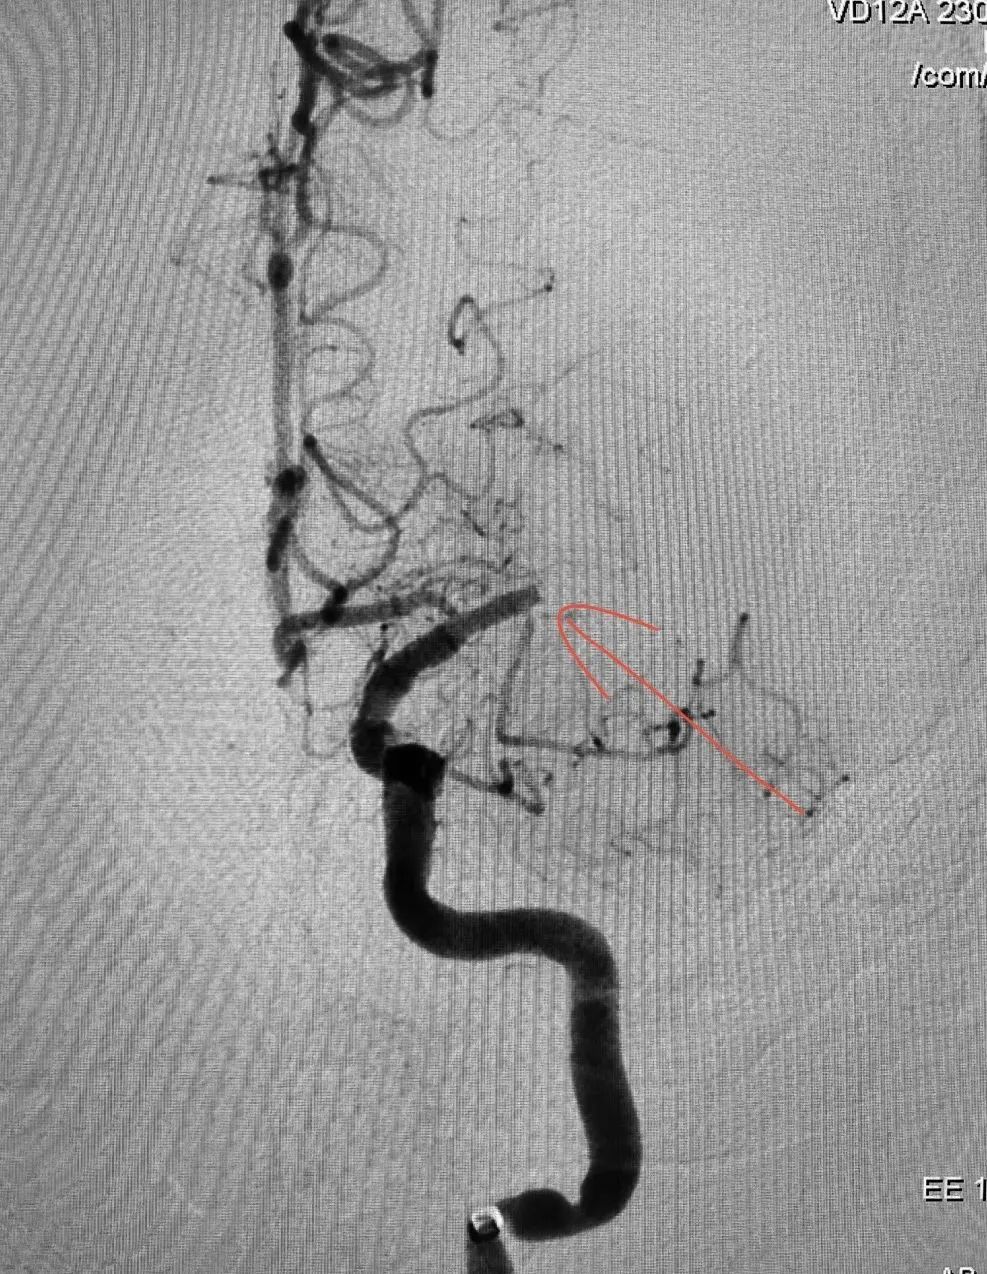

在紧张而有序的准备工作完成后,姜先生的手术于14时40分左右正式开始。手术过程中,医生们成功运用同轴技术超选至闭塞处,并确认真腔后,迅速从中间导管中抽吸出一块红色质地稍硬的血栓。随着血栓的顺利取出,造影结果显示远端血流复流良好。为了确保手术效果的稳定,医生们继续对姜先生进行了30分钟的密切观察。在这期间,造影结果始终显示血管畅通无阻,未再出现闭塞的情况。这标志着此次手术的成功。

▲血管闭塞△ ▲取栓成功后△